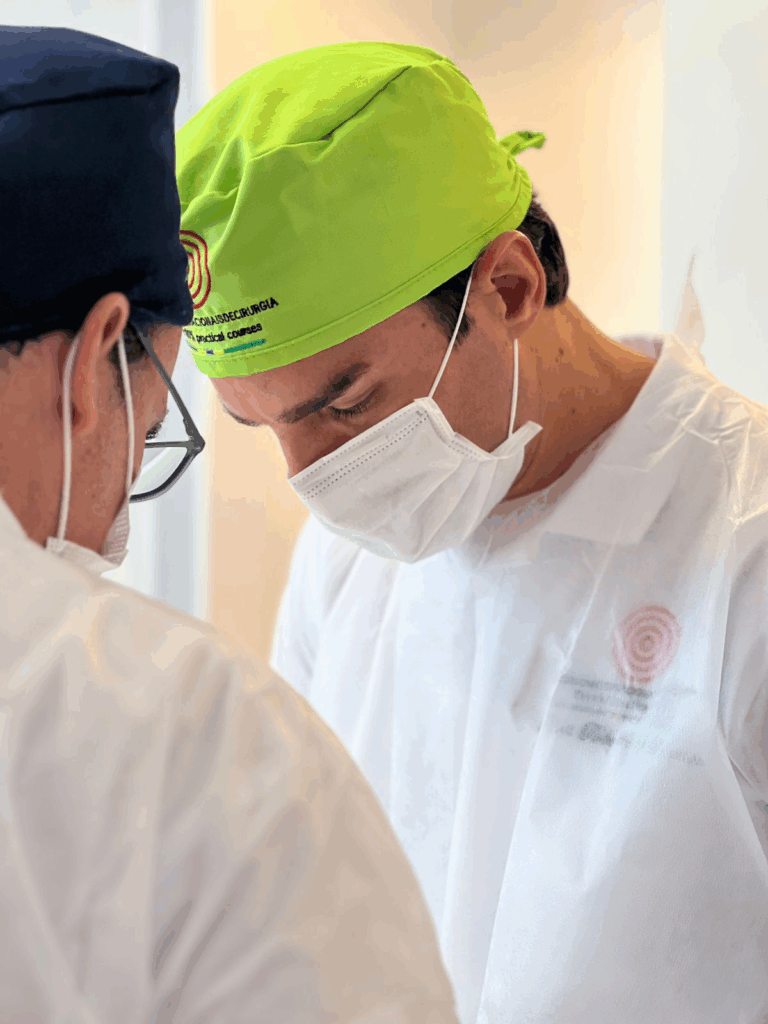

I nostri Tutor

Prof. Fabio G.

Maxillo Facciale, specializzato in implantologia e in chirurgia e traumatologia. È Professore presso l'università di San Paolo e relatore internazionale

SII TU IL PRIMO OPERATORE, SEMPRE! DALL’INIZIO ALLA FINE. IL TUO ASSISTENTE SARA’ UN TUTOR DEDICATO CHE TI SEGUIRA E GUIDERA’ PASSO DOPO PASSO NELLA RISOLUZIONE DEL CASO CHIRURGICO!